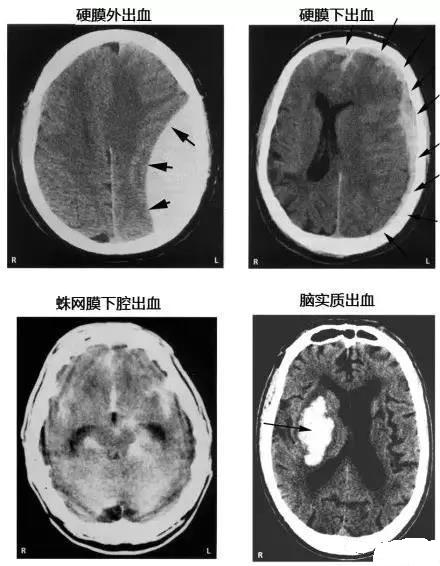

13. 各种颅内出血

点击图片可查看大图详情

15. 几种类型脑出血的CT表现